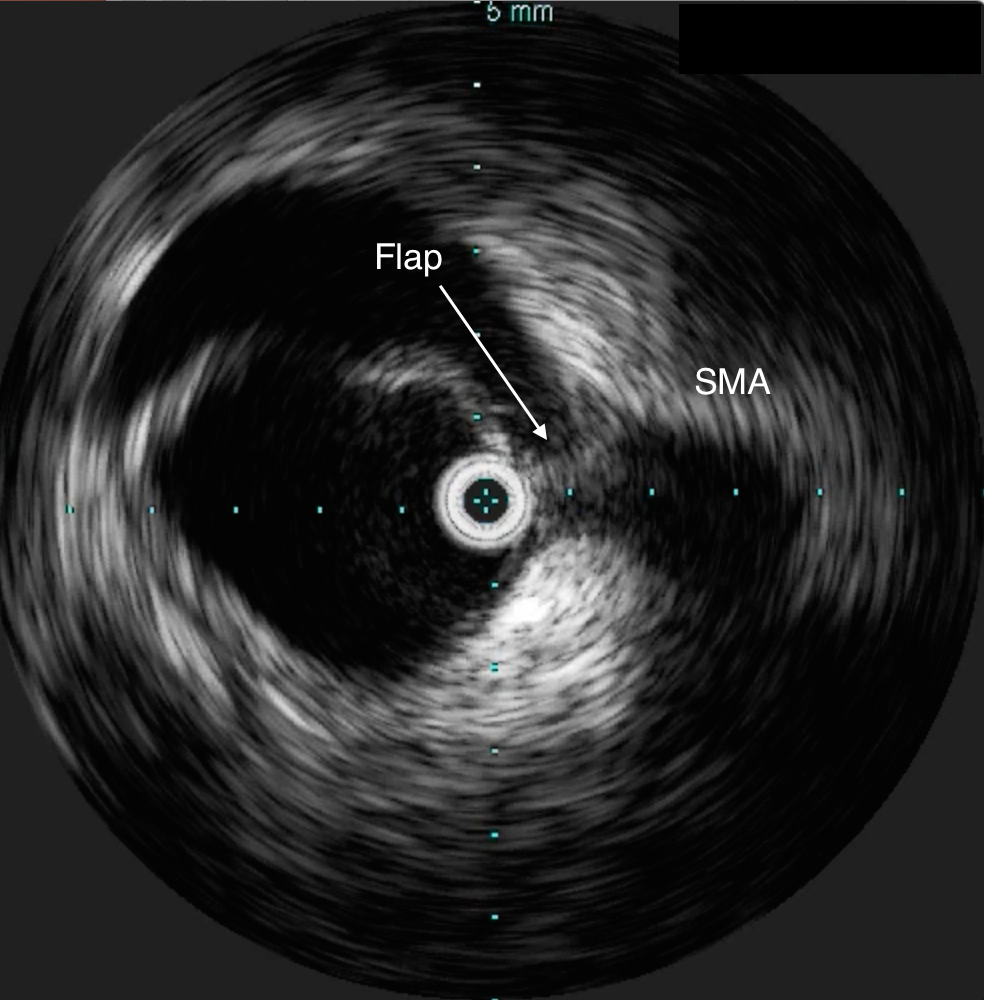

He was taken to the hybrid operating room. Right groin access was achieved and wire access to the arch was achieved. IVUS (Intravascular ultrasound, Volcano) was used to confirm the location of the wire -I believe this is an important adjunct as simply passing the wire doesn’t guarantee travel up the true lumen.

Wire access was achieved across the thrombus. At this point, I had a range of options for thrombectomy including simply aspirating which retracting a catheter. This was not optimal as I could lose subsequent wire access or reenter the false lumen. The other option was an open thrombectomy and patch angioplasty -the thighs were prepped in case we had to harvest vein. Again, in the setting of dissection and going into the mesentery, an open revascularization while feasible, is challenging.

Thrombectomy catheters like Angiojet were available, but I chose to try the Export aspiration catheter (Medtronic). It is simple to set up and goes over a 0.14 wire. It is designed for the coronaries which have a similar lumenal diameter as the SMA. It worked well in this setting in retrieving thrombus which had a pale element that may have indicated some chronicity.

The completion arteriogram was satisfying.

The SMA completely filled as did the celiac axis and both renal arteries. I opted not to treat the right renal artery as we had given 250mL of contrast, and it was filling well without intervention. The patient was making excellent urine and his blood pressure had been maintained with mean arterial pressures above 70mmHg. At this point, IVUS confirmed good deployment of the stent.